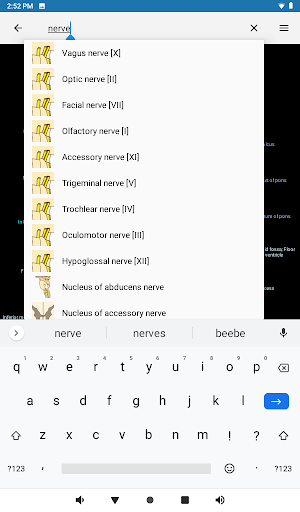

- Mudah menemukan struktur anatomi berkat pencarian indeks

*Meningkatkan kinerja pencarian struktur anatomi

*Temukan bagian anatomi Anda dengan lebih mudah berkat fitur pencarian baru yang lebih intuitif dan canggih